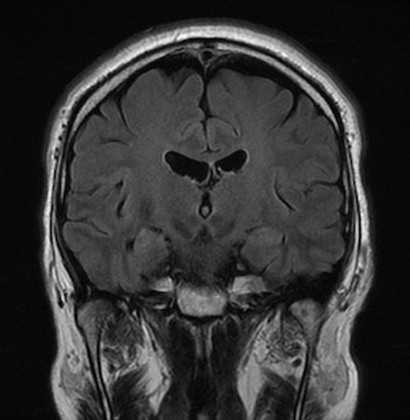

アルツハイマー病のMRIを示します。両側の側頭葉の脳のしわが目立つ(萎縮)ことがお分かりになると思います。

- 正常MRI

- アルツハイマー病のMRI

上の正常のMRIに比べ脳のしわ目立ち、側頭葉の海馬も委縮している